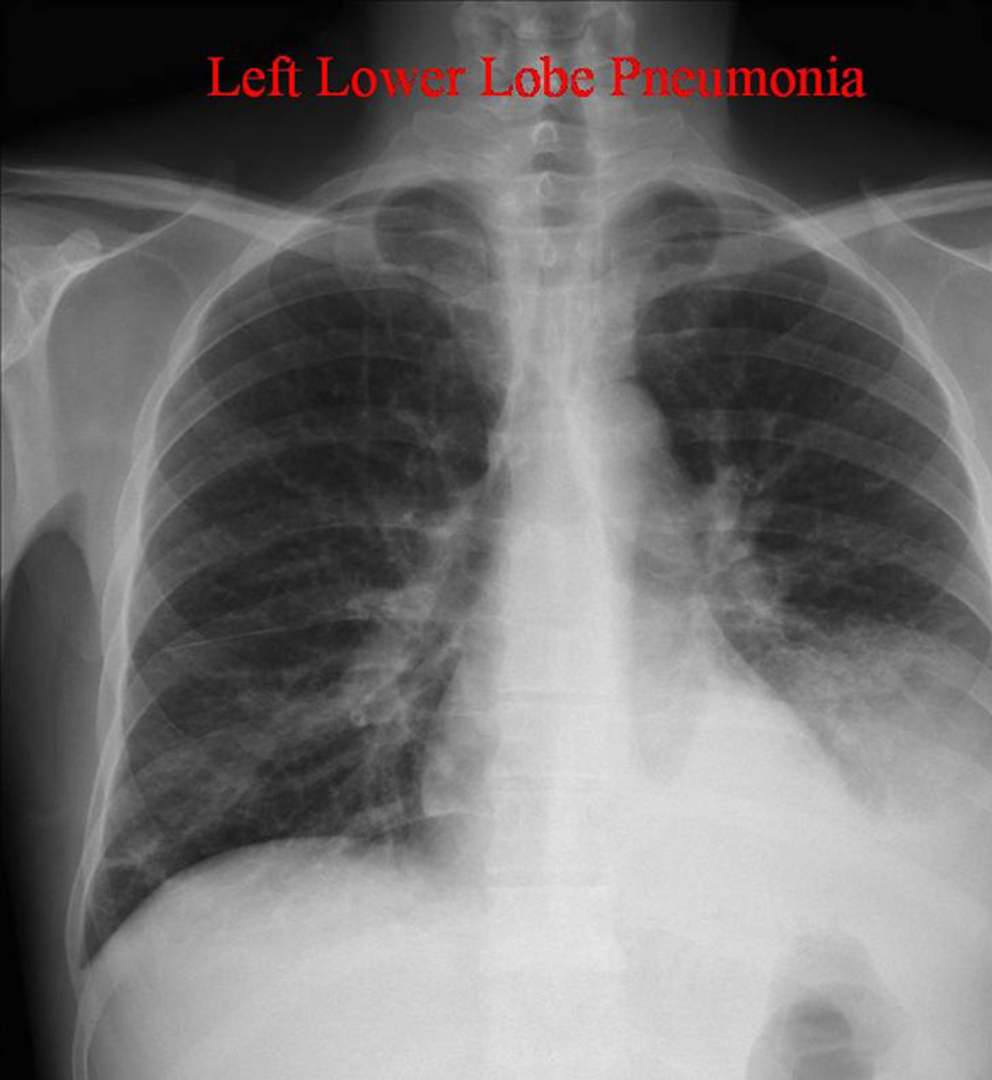

Radiographic finding described as poorly marginated density or “fluffy”

alveolar infilatrate

NOTE: alveolar infiltrates can appear as fluffy or as complete consolidations

Pattern seen on CXR or CT scans when air-filled bronchi become visible against a background of dense lung tissue.

Air bronchogram sign